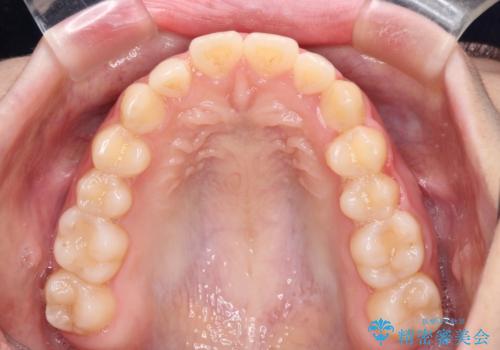

気になる残存乳歯と八重歯 ワイヤー矯正を併用したインビザライン治療

- 八重歯を気にして来院された患者様です。

八重歯のために乳歯が残存していたため、乳歯を抜去して八重歯となっている犬歯を歯列に収めることとしました。

八重歯の移動量が多くなるため、インビザラインと併用してワイヤー矯正を行い、八重歯を改善した後に、上下歯列をインビザラインで整えることとしました。

犬歯は歯根が長くて太いため移動に時間がかかる上に、周囲の歯が八重歯に寄ってきてしまうため、仕上がるまでに期間がかかりました。